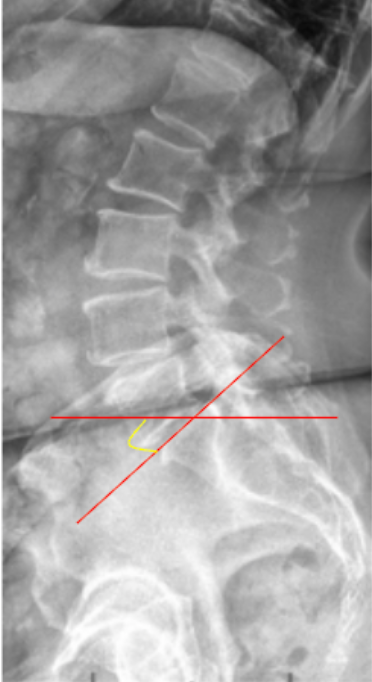

The Lumbosacral Angle (Ferguson’s Angle)—also known as the Sacral Inclination—is a sagittal alignment parameter that quantifies the inclination of the sacrum relative to the horizontal plane.

• Obtain a standing lateral lumbosacral spine X-ray (neutral posture, knees extended).

• Draw a line along the superior endplate of S1—this represents the sacral base.

• Draw a horizontal reference line (parallel to the bottom edge of the image).

• Measure the angle formed between the sacral base line and the horizontal line—this is the Lumbosacral (Ferguson’s) Angle.

• The angle opens anteriorly (downward toward the front of the body).